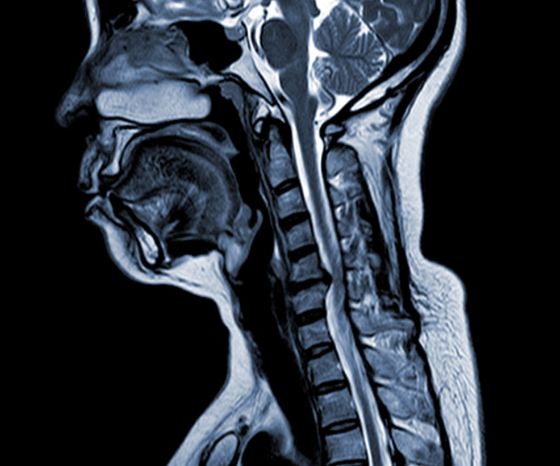

โรคไขสันหลังส่วนคอเสื่อม (CSM)

• ปัจจัยสำคัญ ได้แก่ การเสื่อมของหมอนรองกระดูก การก่อตัวของกระดูกใต้เยื่อหุ้มกระดูก การสร้างกระดูกของเอ็นตามยาวด้านหลัง และการโตของเอ็นฟลาวัม ซึ่งทำให้เกิดการกดทับและแคบของช่องกระดูกสันหลัง